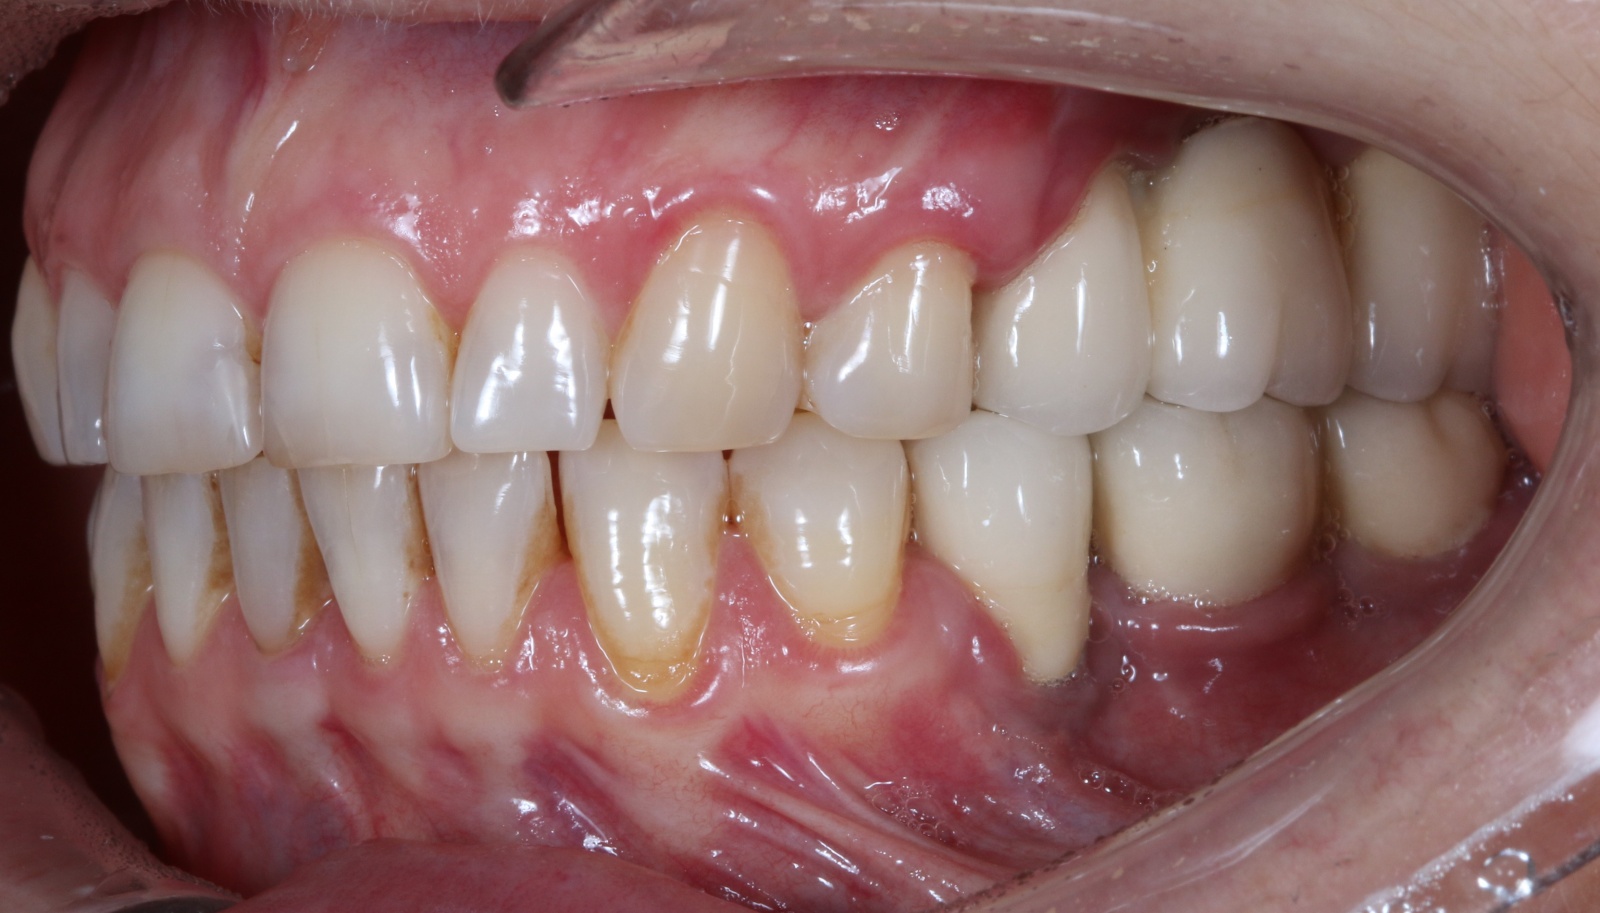

Пациент обратился в клинику с жалобами на забивание пищи и периодические боли в области установленных коронок на нижней челюсти слева. После того, как наш ортопед их снял, сразу стало понятно, в чем же тут проблема.

После снятия коронок в полости рта мы наблюдаем воспаленную гиперемированную десну.

Ниже то, как выглядит десна без формирователей, на начальном этапе снятия слепков.